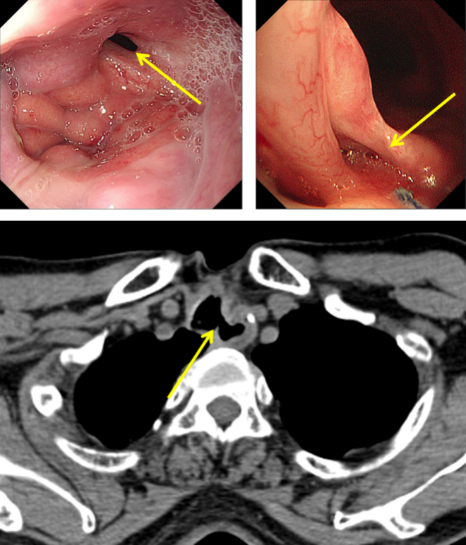

圖1:氣管食管瘺口

經推薦,老秦慕名來到我院胸外科胡楊副主任醫師處就診。經檢查發現,老秦的病情與其他氣管食管瘺患者相比,更為復雜和嚴重:一是瘺口所處位置較為“刁鉆”。患者氣管食管間瘺口位于頸胸交界部位,無論是從頸部或是胸部入路均難以充分暴露瘺口;二是瘺口情況較為糟糕。該患者于外院多次行瘺口修補手術,瘺口附近勢必粘連嚴重、組織結構難以辨認,損傷喉返神經、頸胸部血管等重要結構的風險高;組織血供破壞嚴重,術后缺血壞死風險高;三是患者營養嚴重不足。該患者由于“氣管食管瘺”已兩年未經口進食,身體非常虛弱。